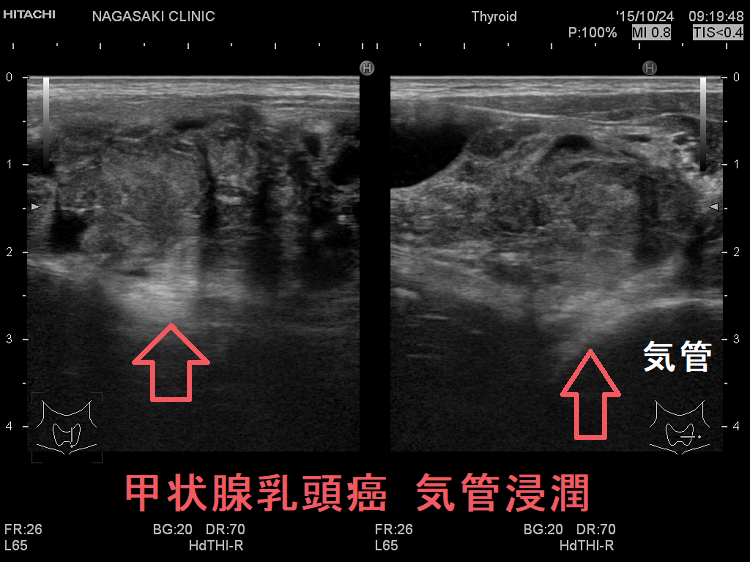

周囲の線維組織・脂肪組織・甲状胸筋・顕微鏡的な反回神経への浸潤(最小限の浸潤:EX1)は生存率に無関係とされます。

甲状腺の被膜外への広い浸潤(腫瘍を削り取ることができる大規模な浸潤:Ex2)は、甲状腺乳頭癌の予後不良因子。

[World J Surg. 2012 Jun;36(6):1274-8.]

肉眼的に甲状腺の外(気管・食道、反回神経)まで浸潤した場合(EX3)、10年生存率は75%程とされます。

Ex3の甲状腺乳頭癌患者は、Ex2の患者よりも有意に

- 無病生存期間・疾患特異的生存期間が短い

- 局所再発までの期間が短い

- 遠隔転移による死亡までの時間が短い

Ex3で気管・食道へ浸潤した場合、反回神経だけの浸潤より疾患特異的生存期間が短い。

[World J Surg. 2012 Jun;36(6):1231-40.](第56回 日本甲状腺学会 P2-098 甲状腺外浸潤よりみた甲状腺乳頭癌の予後予測)